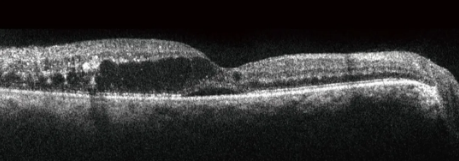

糖尿病视网膜病变眼底OCT影像图

DR 可见浆液性网脱+囊样网脱,出现液性空腔

DR 视网膜隆起增厚,层间可见积液

DR 视网膜隆起增厚,层间可见积液与渗出;RPE连续性破坏

DR 视网膜层间水肿